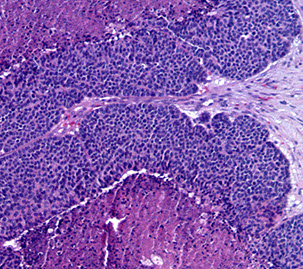

Acinic Cell Carcinoma

Malignant neoplasm with cells resembling normal serous acinar cells;

Parotids(4/5) > Submandibular > Minor salivary glands, F>M

May be bilateral or multicentric (like Warthin’s)

Tumors are generally small discrete lesions

- there is no b9 counterpart (acinic cell adenoma)

- grossly firm, circumscribed most of the time

Variable architecture (types) and cell morphology

Clear cytoplasm generally, but can be solid or vacuolated

- if cytoplasmic vacuoles present, may stain PAS (+); however they are just secretory granules and not mucin (as in MEC)

- usualy basophilic c lots of lymphoid infiltrate

- can look a little like thyroid

Can be in sheets or microcystic, glandular, follicular or papillary patterns

Usually few mitoses and little anaplasia

IHC: (+) PAS, PASD, (clear cells are PAS and mucin neg), keratin, amylase, transferrin, IgA, proline-rich protein, ANO1 (anoctamin-1)/DOG1 (Discovered On GIST-1), SOX10

- Negative GCDFP-15, MUC1, BRST-2 and mammaglobin and HER2

Clinical course dependent of degree of pleomorphism, though not well established

10-15% with LN mets, up to 35% recurrence

Both associated with worse prognosis

- otherwise fairly good 5-year survival (low-risk)

Acinic cell carcinoma